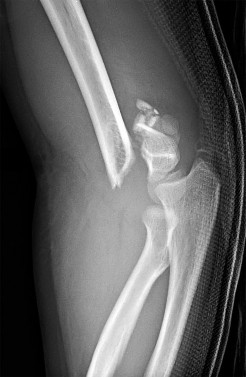

A 5-year-old boy presents with an extension-type Gartland III supracondylar humerus fracture after a fall.

On examination, his hand is well-perfused (pink) with brisk capillary refill, but the radial pulse is absent. What is the most appropriate initial management?